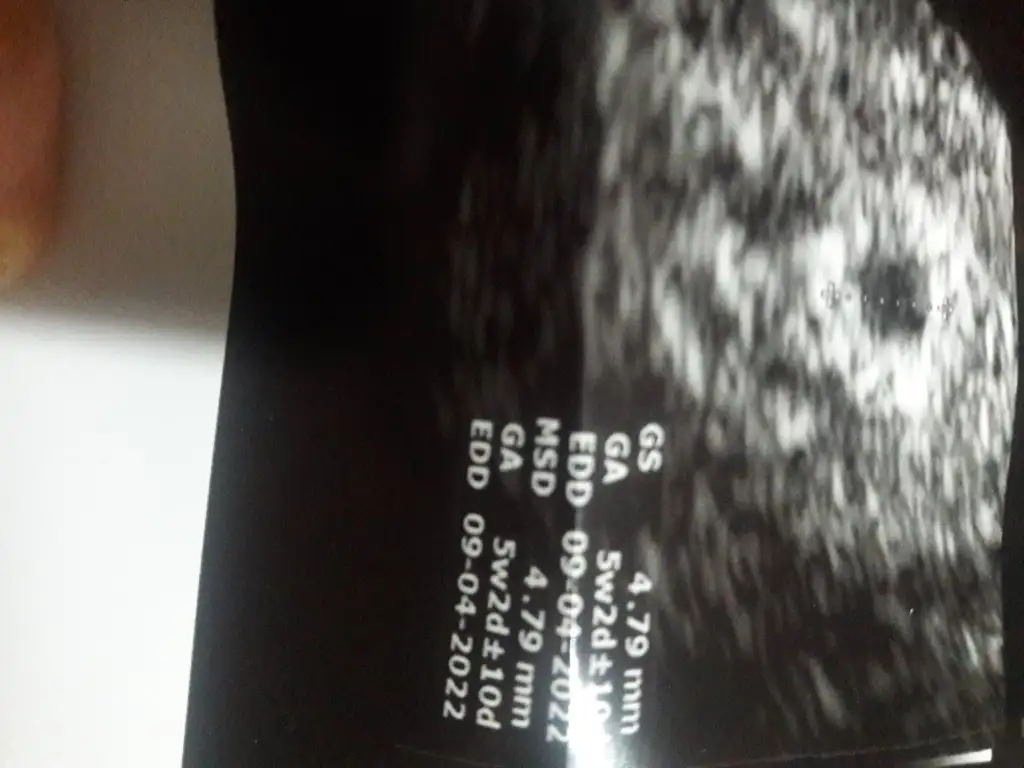

Amin canım dualarım hepimiz için benim ultrasona bakarmisin 5+2 mi anlamadım yolk keseside 1.84mm . 2.5 in altı sağlıksız gebelik sayılıyormus öyle okudum bi yerde😔

5 hafta 2 günlük kuzum kese 4cm yolk 1.84 mm oda 5 haftalık gebelik için gayet normal

Bugün ultrason sonucum bu canım. 9temmuz transferim oldu.3adet dondurulmuş emrio transferiydi. Transfer sonrası 9.gün kanamam oldu 2gun devam etti kanamamın başladığı gün kan verdim

18temmuz 44.1

21temmuz 65.76

23temmuz 48.96

27temmuz 141.08

29temmuz 334.36

02Agustos 1177.91

06Agustos 4175 cikti

Doktora göre 7hftlık olması lazımdı ama 5hftlik görünüyo dedi 😏